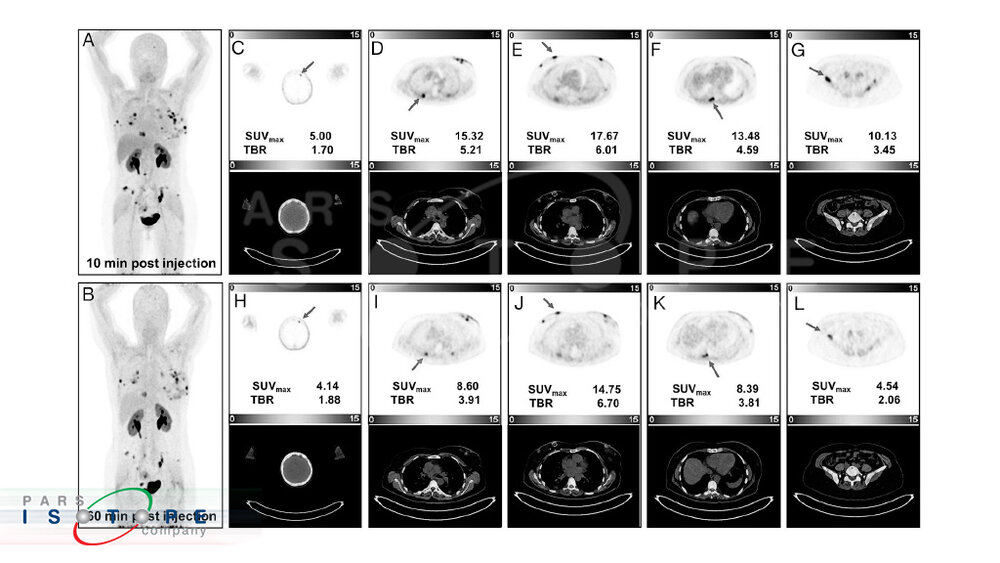

این رادیودارو با توجه به قدرت تشخیص بالایی که دارد، گزینه جذابی برای انجام تحقیقات جدید محسوب می‌شود. اخیرا با استفاده از این رادیودارو یک مطالعه در خصوص تصویربرداری پت اسکن زودهنگام انجام شده است. در این مورد مطالعاتی، خانمی 55 ساله، با آدنوکارسینومای متاستاتیک پستان و سابقه برداشتن تومور اولیه و ضایعات عود کننده متعدد، تحت تصویربرداری زودهنگام و دیر هنگام پت اسکن با رادیوداروی Ga-68-FAP-2286 قرار گرفت. اسکن‌های تصویربرداری در فواصل 10 و 60 دقیقه پس از تزریق انجام شد. نتایج تصویربرداری نشان می‌دهد که ۱۱ ضایعه عود موضعی، یک متاستاز مغزی، یک ضایعه غدد لنفاوی، یک ضایعه ریه و ۱۳ متاستاز در سیستم اسکلتی وجود دارد و همچنین مقادیر SUVmax و TBR (نسبت تومور به پس زمینه) در تصویربرداری 10 دقیقه‌ای پس از تزریق در مقایسه با تصویربرداری 60 دقیقه‌ای پس از تزریق بالاتر بود.

با وجود مزایای متعددی که Ga-68-FAP-2286 در مقایسه با سایر رادیوداروهای تشخیصی مانند FDG، Ga-68-FAP-02,04,46 دارد، مطالعات برای اولین بار نشان می‌دهد که زمان تصویربرداری PET/CT برای این رادیودارو می‌تواند به اندازه 10 دقیقه پس از تزریق کوتاه باشد.